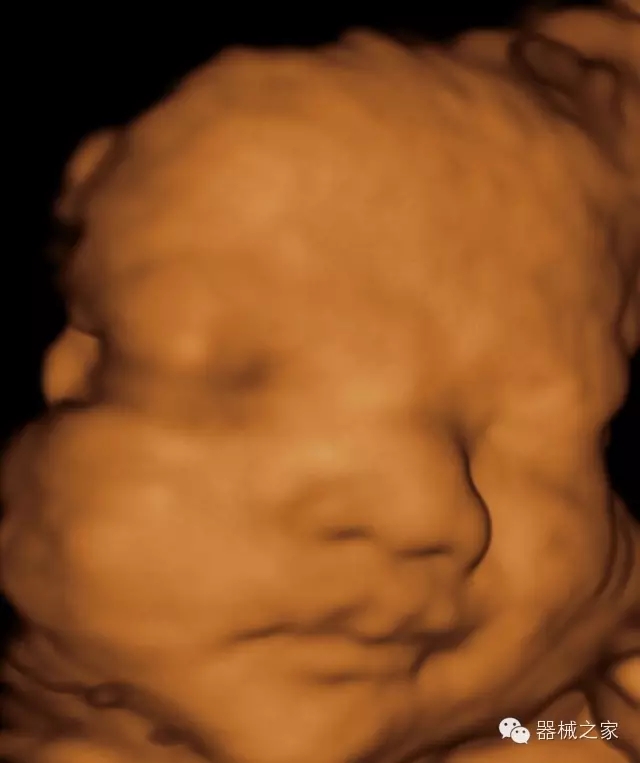

臨床圖片賞析

產(chǎn)品特點

·高效3D/4D成像技術(shù):高速的4D幀頻,豐富的3D成像模式,智能斷層切片功能;